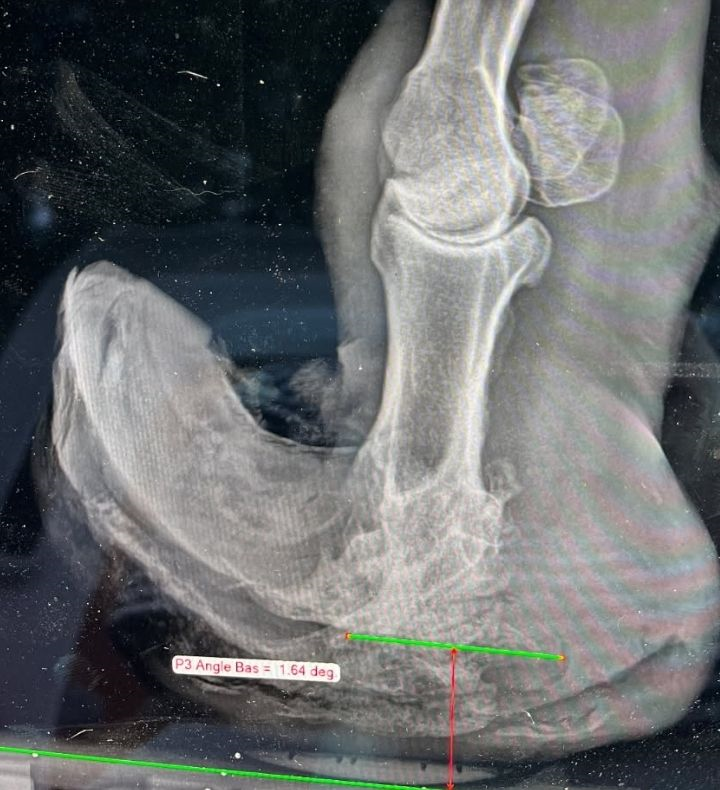

- Un lourd passé : lorsqu’il était poulain, il a subi un traumatisme grave à un antérieur. Les examens vétérinaires ont révélé une double fracture des phalanges (P2 et P3). Résultat : son sabot est sévèrement déformé, l’empêchant de poser son pied correctement.

Résultats de la radiographie :

- Arthrodèse complète de l’articulation interphalangienne distale (P2–P3).

- Ostéolyse très marquée (destruction de l’os) de la troisième phalange.